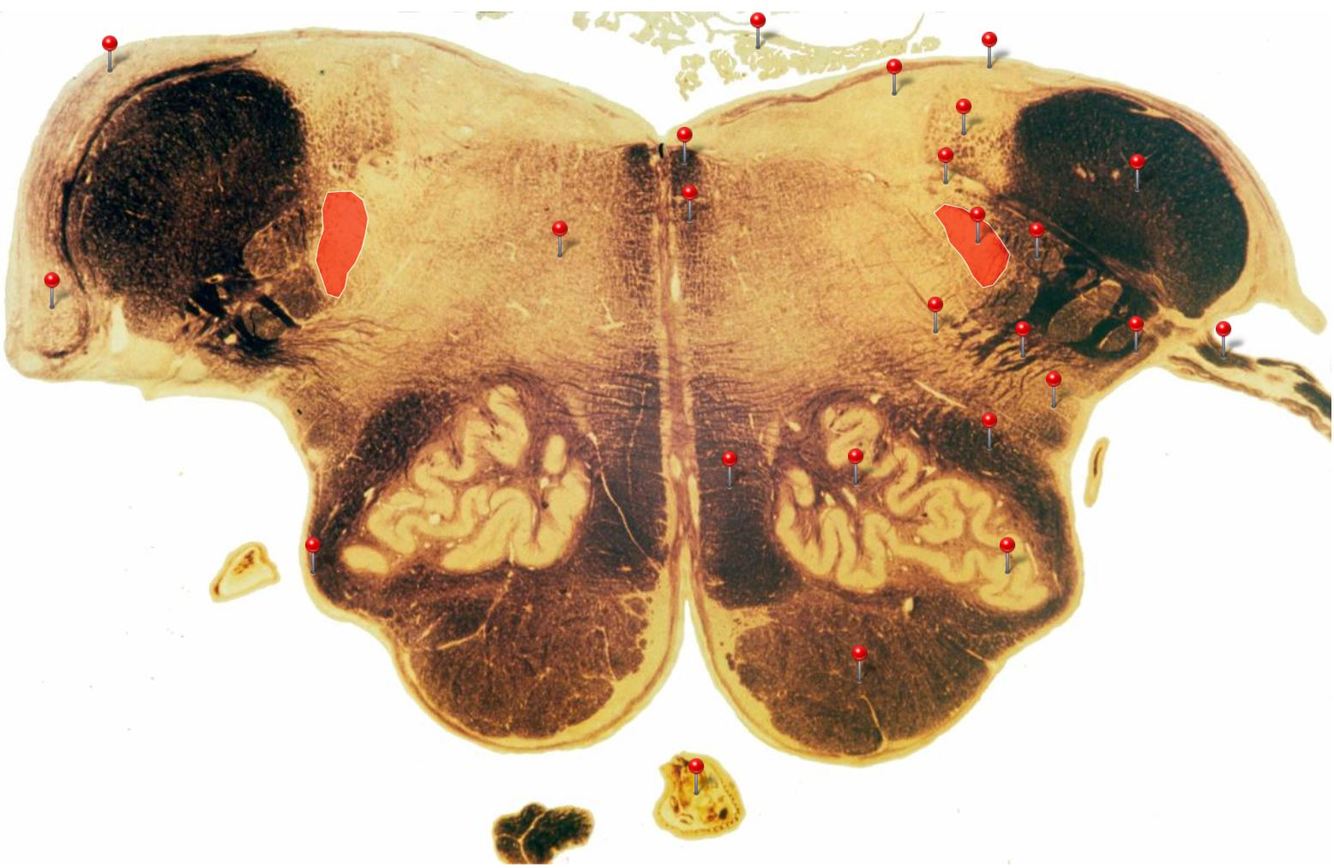

Caudal Midbrain

Transmits auditory info from the inferior colliculus to the medial geniculate nucleus of the thalamus

Edinger Westphal Nucleus

Contains the cell bodies of the preganglionic parasympathetic (GVE) fibres of the oculomotor n. (CN III)

Corticospinal Tract

Controls precision and speed of skilled movements involving the distal muscles of the contralateral limbs, particularly those of the hands and fingers

Rubrospinal Tract

Assists in the control of movements of the hands and fingers

Oculomotor Nucleus

Neurons give rise to GSE fibres of the oculomotor nerve (CN III) which supply extraocular muscles (4 out of the 6, as well as some fibres of the levator palpebrae superioris m.)

Spinothalamic Tract

Transmits pain and temperature sensations from the spinal cord to the thalamus

Superior Colliculus

Important relay centre for visual reflexes

Periaqueductal Gray (PAG)

Important centre in modulating pain transmission in the spinal cord, particularly in conditions of extreme stress (indirectly through connections with reticular formation)

Medial Longitudinal Fasciculus

Pathway through which eye movements are coordinated with changes in head position